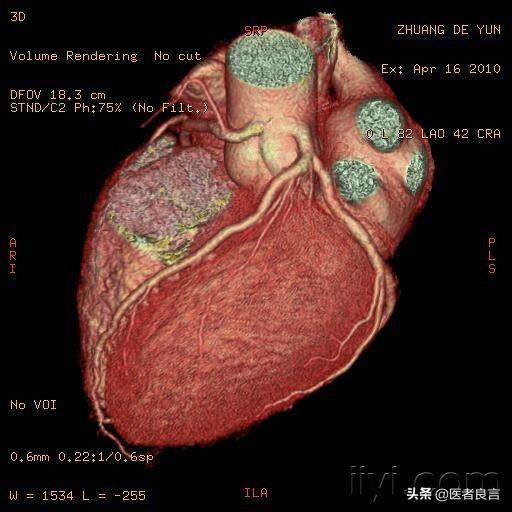

3. la coronarographie :

La coronarographie varie selon les régions et les hôpitaux ; dans l'Anhui, elle coûte environ 5 000 yuans, dans les grandes villes du sud, elle devrait être plus chère ; la coronarographie est principalement utilisée pour confirmer le diagnostic de maladie coronarienne.

Le diagnostic de la maladie coronarienne peut consister en un électrocardiogramme à 30 dollars ou en une imagerie à 4 000 dollars. Bien que l'imagerie cardiaque soit l'étalon-or pour le diagnostic de la maladie coronarienne, elle n'est pas destinée à être administrée à tout le monde pour diagnostiquer la maladie coronarienne.

Nous diagnostiquons la maladie coronarienne : en fonction des symptômes, des facteurs de risque, des électrocardiogrammes, parfois de la pression artérielle combinée à des électrocardiogrammes ambulatoires, des tests d'effort, une angiographie coronarienne ou une angiographie coronarienne.

Parfois, nous pouvons diagnostiquer une maladie coronarienne sur la base de symptômes et d'un ECG de 30 pièces, ce qui est suffisant, sans qu'il soit nécessaire de prendre le risque de recourir à l'imagerie, qui est après tout un examen invasif comportant des risques de saignement, d'hématome, de piégeage, de néphrotoxicité, d'allergie, etc.